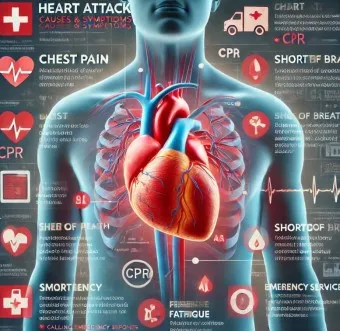

위험 신호와 응급상황

다음과 같은 증상이 동반될 경우 즉시 전문의의 진찰이 필요해요:

1. 응급 상황의 기준

- 심한 호흡곤란이 동반되는 경우

- 식은땀과 함께 가슴 통증 발생

- 어지럼증과 실신 증상 동반

- 맥박이 불규칙하게 뛰는 경우

2. 위험 신호

- 증상의 지속 시간이 30분 이상

- 일주일에 3회 이상 증상 발생

- 운동하지 않을 때도 심박수 120회/분 이상

- 안정을 취해도 증상이 호전되지 않는 경우